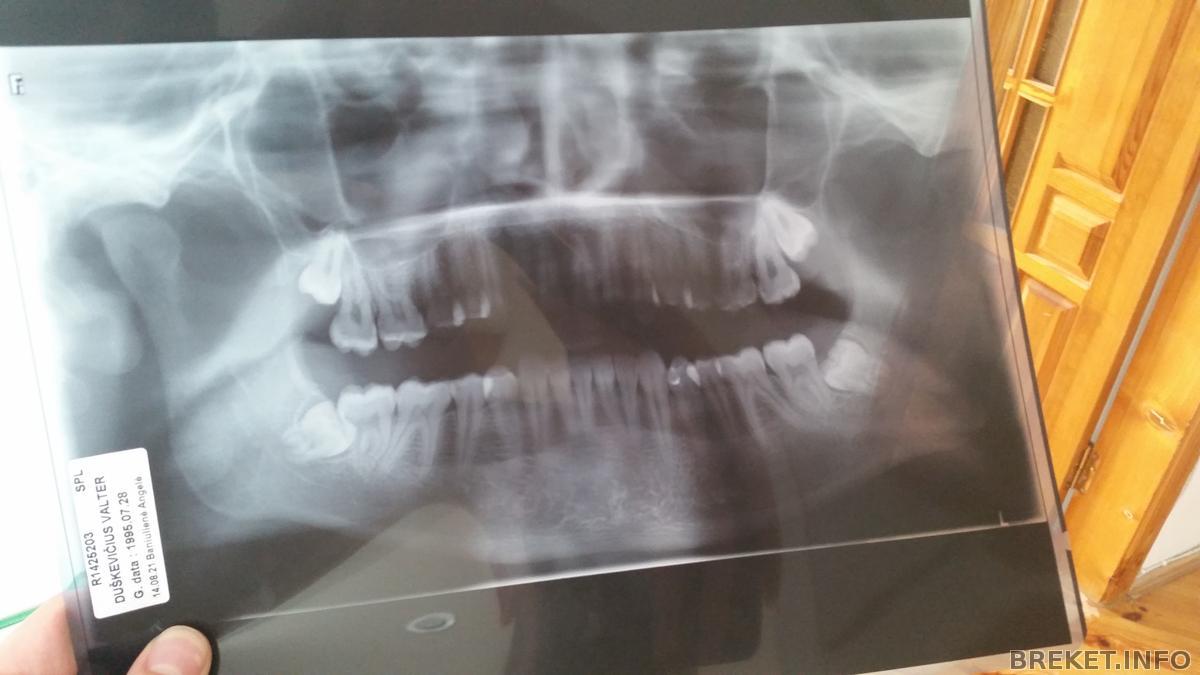

Завтра еду на удаление:( сказали что возможно 2 сразу удалят.покажу снимок ибо мне надо чтобы он сказал не будут ли они мешать когда их удалят.и еще вопрос как быстро можно брекеты поставить после удаления зубов? Как долго дырка заживает?

Снимок в студию

Walter да, нижние восьмерки удалять срочно)))